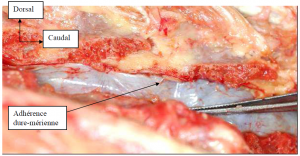

Photo INSERTIONS DE LA DURE-MERE SUR LE RACHIS Une anatomie redécouverte 29